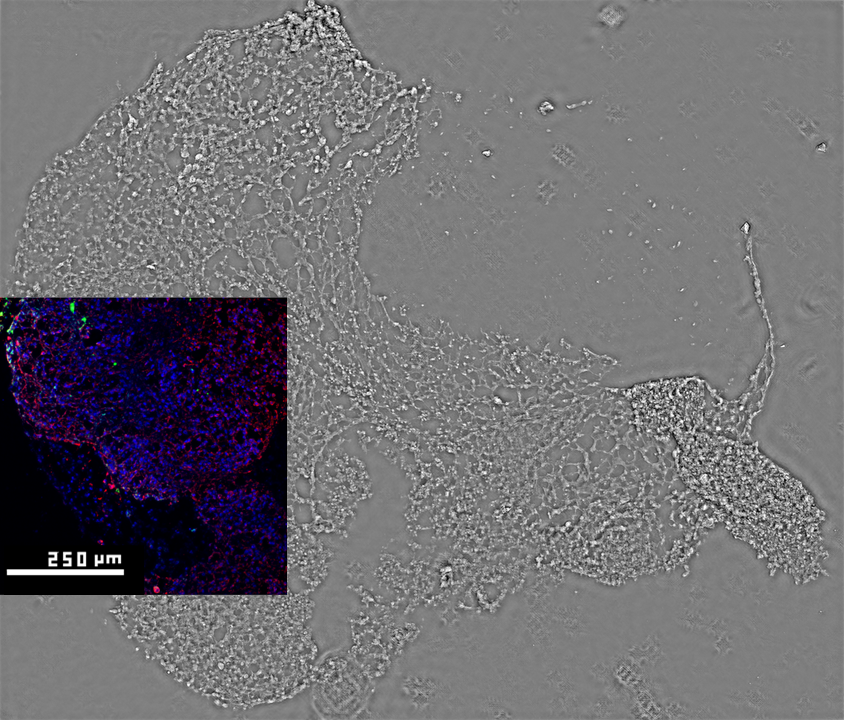

[January 2026] We are excited to share our new publication: „High Space-bandwidth Product Label-free Examination of iPSC-derived Brain Organoids via Fourier Ptychographic Microscopy” in IEEE Journal of Selected Topics in Quantum Electronics.

What we imaged?

Brain organoids are miniature, three-dimensional models of the human cortex grown from stem cells and increasingly used to study disease and test drugs. In this work, we show that they can be visualized in their entirety, label-free, using Fourier ptychographic microscopy (FPM).

The technique & novelty

This computational technique combines multiple simple images into a single high-resolution, wide-field view. This allows us to image entire thin organoid slices with subcellular resolution using a low-cost, modified light microscope and an LED array. We then merge our phase images with conventional fluorescence microscopy, revealing, for example, that nuclei in neurogenic zones have higher phase values, reflecting higher cellular density and division activity. Our approach paves the way for cheaper, faster, and potentially fully label-free studies of brain development and disease modeling.

Team

This publication is the outcome of a fantastic collaboration between QCI Lab members: Mikołaj Krysa, Mikołaj Rogalski, Piotr Arcab, Kamil Kalinowski, Piotr Zdańkowski, Maciej Trusiak, together with Mukesh Varshney, Pawel Goclowski, Vishesh Dubey, Balpreet Singh Ahluwalia. Many thanks to our amazing collaborators!

Funding

This work was supported by The National Centre for Research and Development (Project No. WPC3/2022/47/INTENCITY/2024), and by NCN National Science Centre, Poland (2020/39/D/ST7/03236)